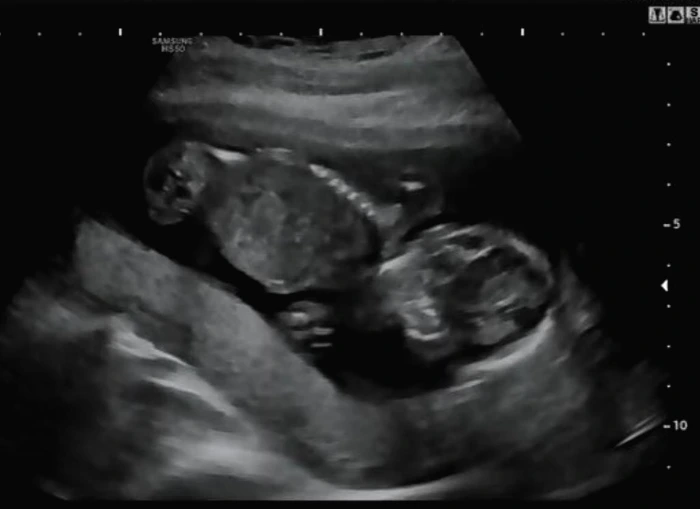

일반적으로 임신 12주 차부터는 복부 초음파로 태아를 확인이 가능하다. 나는 8주 차 질 초음파 상으로 태아의 상태를 확인한 이후 복부초음파로 추가 확인을 했다. 임신 초기에는 질초음파를 이용하여 태아를 확인하는 것이 정확하며 복부초음파는 초기에 적합하지 않다. 태아의 크기가 너무 작아 복부초음파로 확인하기에는 정확한 확인이 불가할 수 있어서 임신 초기가 지나고 나서 복부초음파를 이용한다.

BPD(태아의 머리둘레)와 AC(태아의 복부둘레)를 측정하고 이후 심장소리를 확인했다. BPD와 AC로 이용하여 주수에 맞게 잘 자라고 있는지 확인했다. 아기는 여전히 잘 자라고 있다고 일정하게 심장소리를 들려주며 초음파 상으로 열심히 움직이고 있었다.